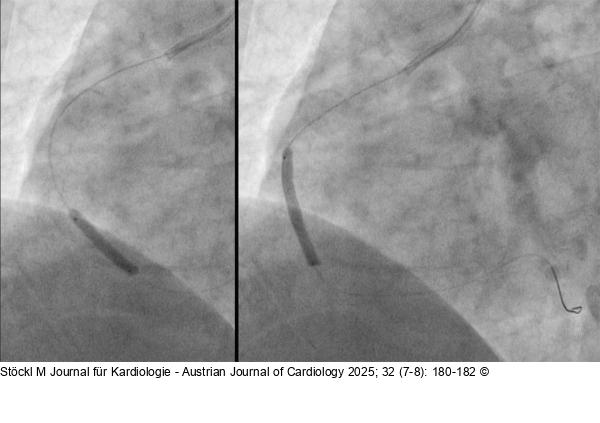

Abbildung 4: RCA: Drug Eluting Balloons RCA: Drug Eluting Balloons (DEBs) SELUTION SLR™ 3,5/20 mm und 3,5/30 mm (Cordis) |

Abbildung 4: RCA: Drug Eluting Balloons

RCA: Drug Eluting Balloons (DEBs) SELUTION SLR™ 3,5/20 mm und 3,5/30 mm (Cordis) |